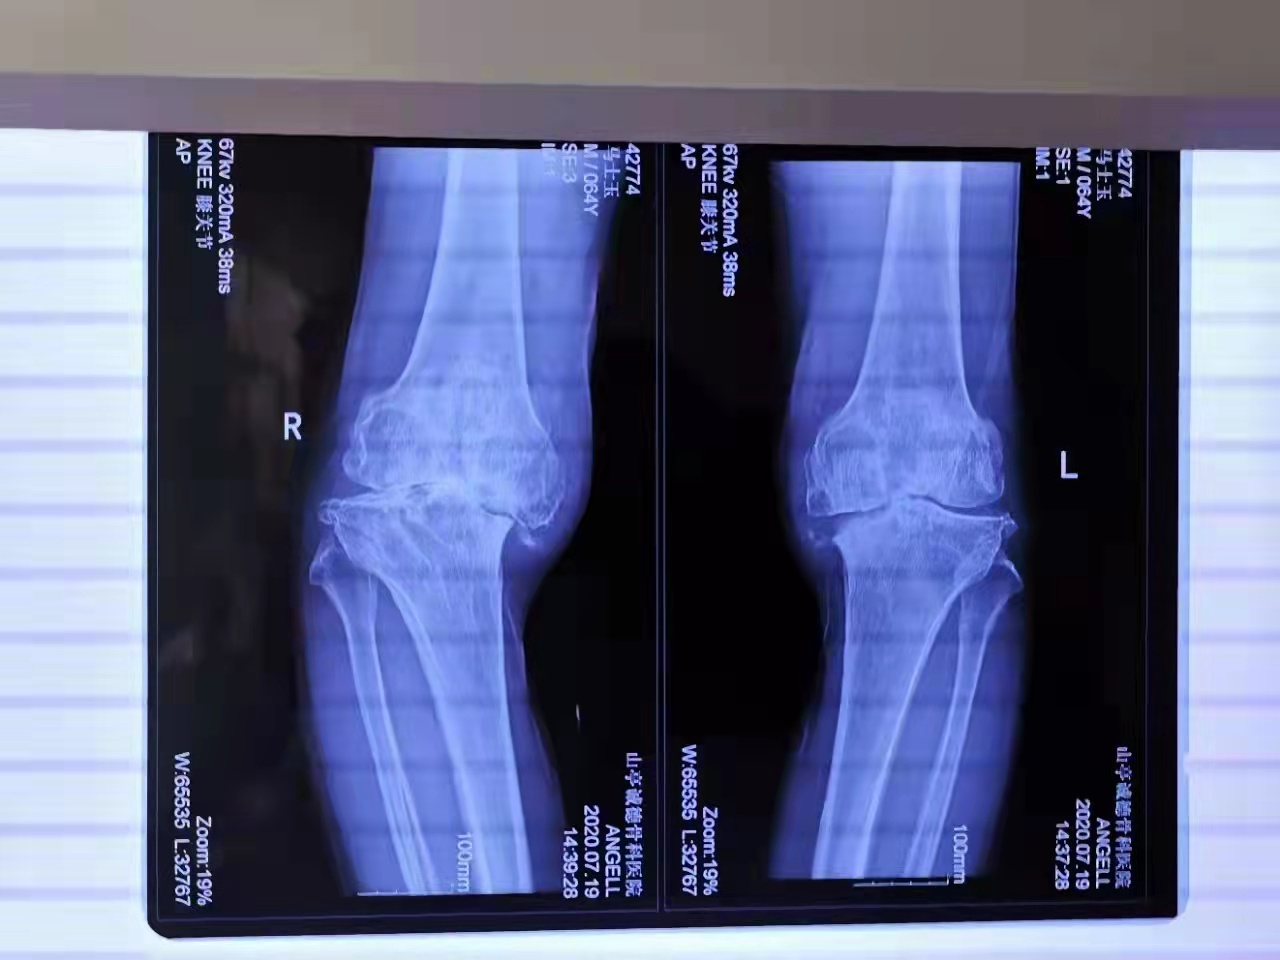

馬先生今年64歲,家住山亭區(qū)。換患雙膝關(guān)節(jié)骨性關(guān)節(jié)炎,造成下肢嚴(yán)重畸形,行走困難,疼痛難忍。在13歲時(shí)受傷骨折,沒有治療導(dǎo)致關(guān)節(jié)畸形、骨缺損。多年來傷病的困擾讓他痛不欲生。生活在困惑的黑暗中。